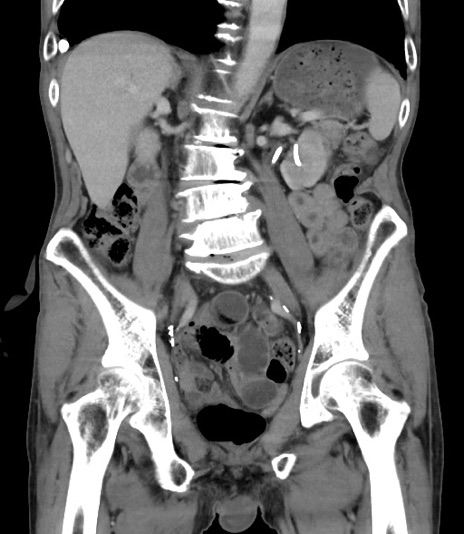

症例3(冠状断像)

【症例】 70歳代男性

【主訴】右鼠径部腫瘤、疼痛

【現病歴】本日朝より上記主訴あり、受診。

【既往歴】膀胱癌にて膀胱全摘、両側尿管皮膚瘻

【データ】WBC 5600、CRP 0.56